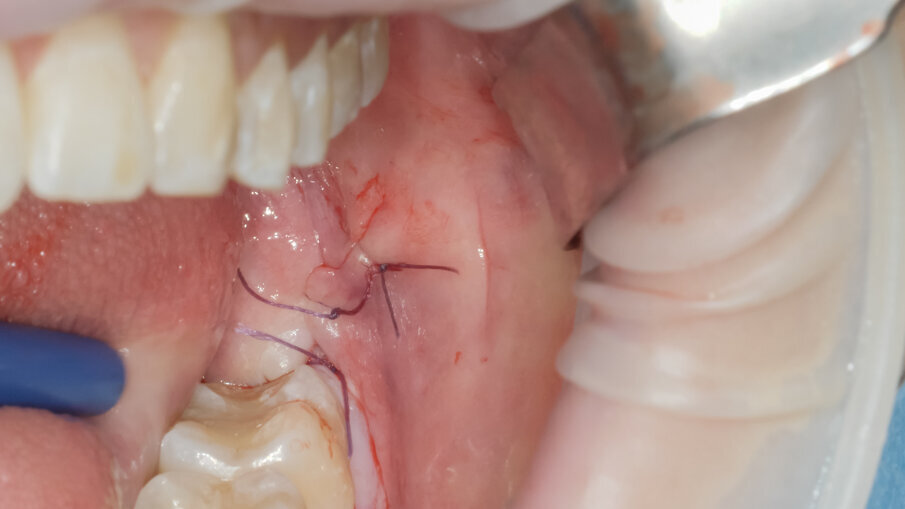

La scelta condivisa è quella di utilizzare la tecnologia piezolettrica per le fasi di odontotomia, solo nelle zone di difficile accesso o in prossimità di strutture anatomiche a rischio come il nervo alveolare inferiore. Per la fase di lussazione si è applicato il protocollo descritto da Fontanella utilizzando il nuovo inserto EXL1 (Figg. 6, 7). Questo inserto insieme agli altri due inserti lussativi (EXL2, EXL3) hanno la particolarità di sfruttare l’impulso piezoelettrico associato al movimento lussativo dell’inserto montato sul manipolo. La cavità residua è stata gestita rimuovendo i residui di sacco follicolare e detergendo il sito post estrattivo sfruttando l’effetto cavitazionale della tecnologia piezoelettirca (Fig. 8). Il lembo riposizionato è stato suturato con chiusura per prima intenzione con punti singoli riassorbibili 4/0 (Fig. 9). Al controllo post operatorio la ferita presentava una guarigione nella norma, e la paziente riferiva un post operatorio senza particolare gonfiore e con assunzione di antidolorifico solo nel primo giorno post chirurgico